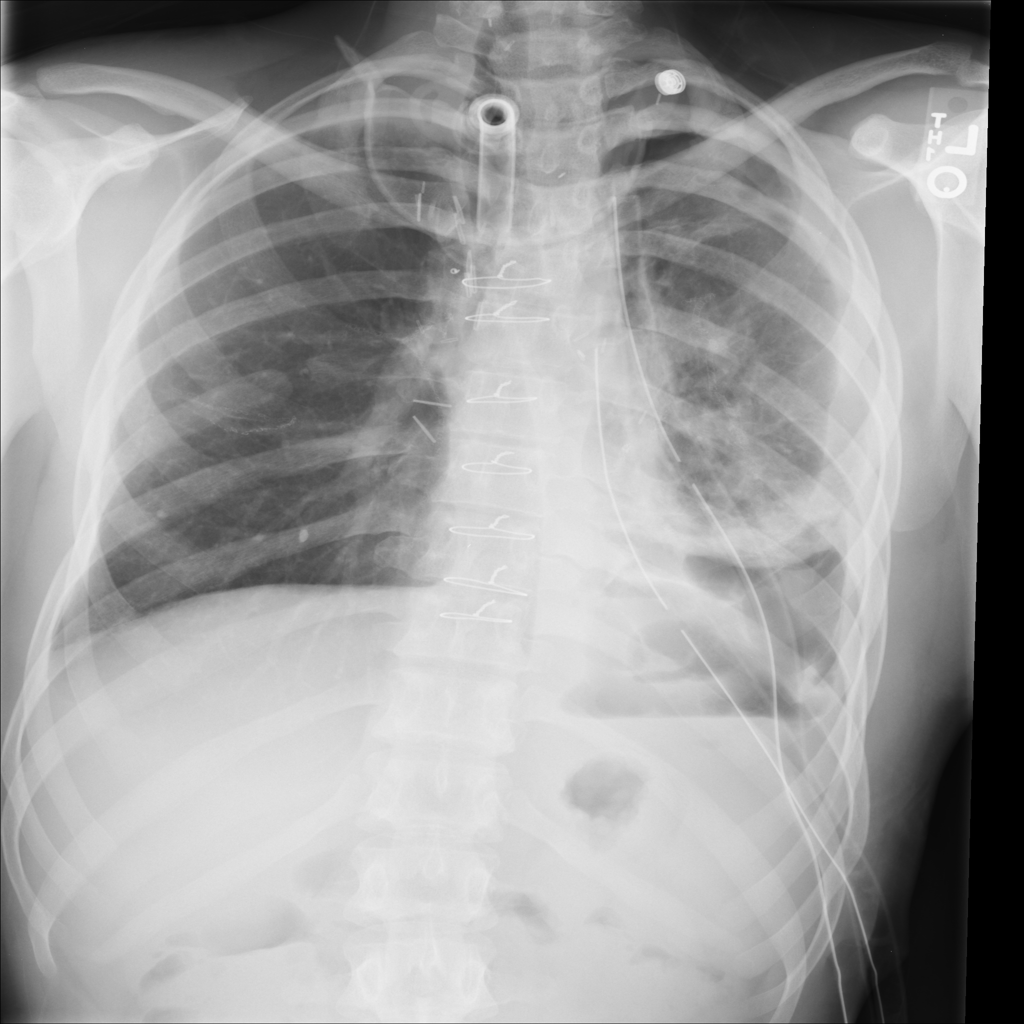

PAT-4639 · IMG-012Pneumothorax

PAT-4639 · IMG-012

AP